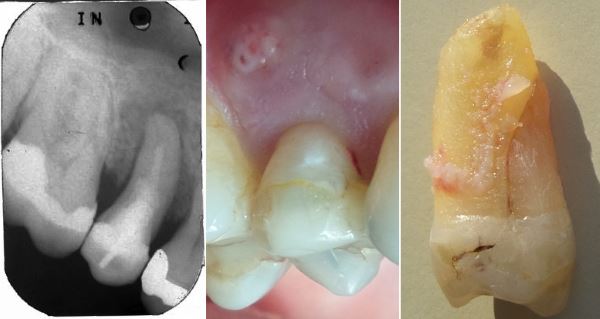

Anamnese: Seit einiger Zeit schmerzt das Zahnfleisch rund um den Zahn.

links: Beide Wurzelspitzen sind gespalten

Mitte: mesiale Wurzel längsgespalten.

rechts: distale Wurzel längsgespalten

Der Grund für solche Wurzelfrakturen ist höchst rätselhaft. Vielleicht werden einige Wurzeln nach der Wurzelbehandlung sehr brüchig? Schrumpft das Dentin wegen der Austrocknung? Gibt es eine strukturbiologische Schwachstelle? Oder schwächen gewisse Reinigungstechniken bei der Wurzelbehandlung die Wurzel so sehr?